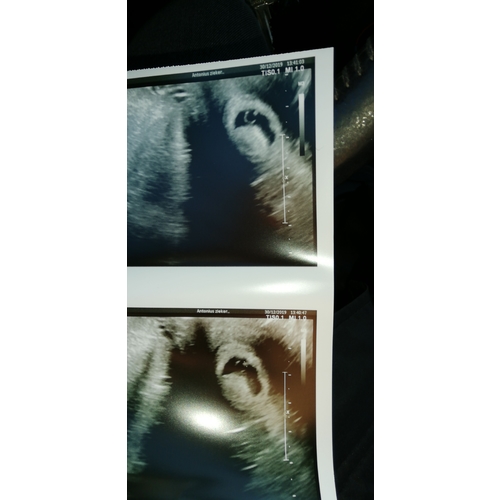

Dit was afgelopen zomer. Ik was net geen 6w zwanger, klopte een hartje. Ik ...

Ja mooie foto was het niet hihi was echt nog zo weinig te zien, maar al wel kloppend hartje.

De zwangerschap, bevalling en haar start waren heeeel heftig... maar dat heeft niks met dit te maken hihi. Ze is nu een gezonde heerlijke meid 🥰